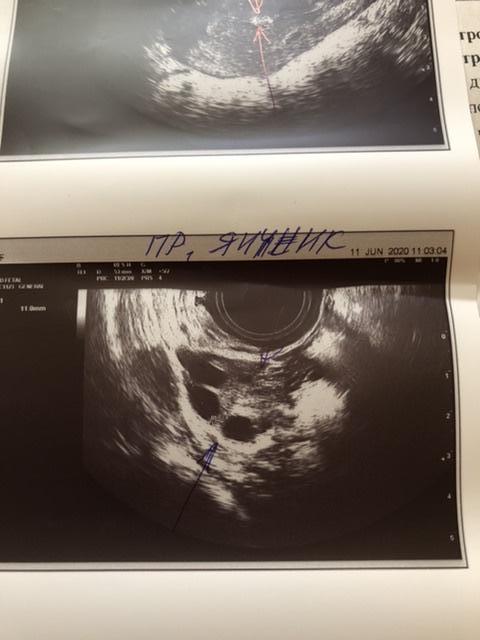

Идёт 4 цикл планирования , решила сходить на узи, на 1 сказали подозрение на полип и киста правого яичника, сегодня была на 2 узи. Кисты в Правом яичнике нет ! Правый яичник с фолликулами до 11 мм, а вот левый содержит доминантный фолликул 20 мм, как думаете когда будет овуляция ? Но , опять увидели это включение размером 7 на 4 мм, сказали с полипом не забеременеешь ! Вопрос кто делал гистероскопию ? Как она прошла ? Или может кто-то забеременел с полипом ? И все же как думаете когда совуляционирует левый яичник ? Эндометрий 10 мм это хороший показатель ?